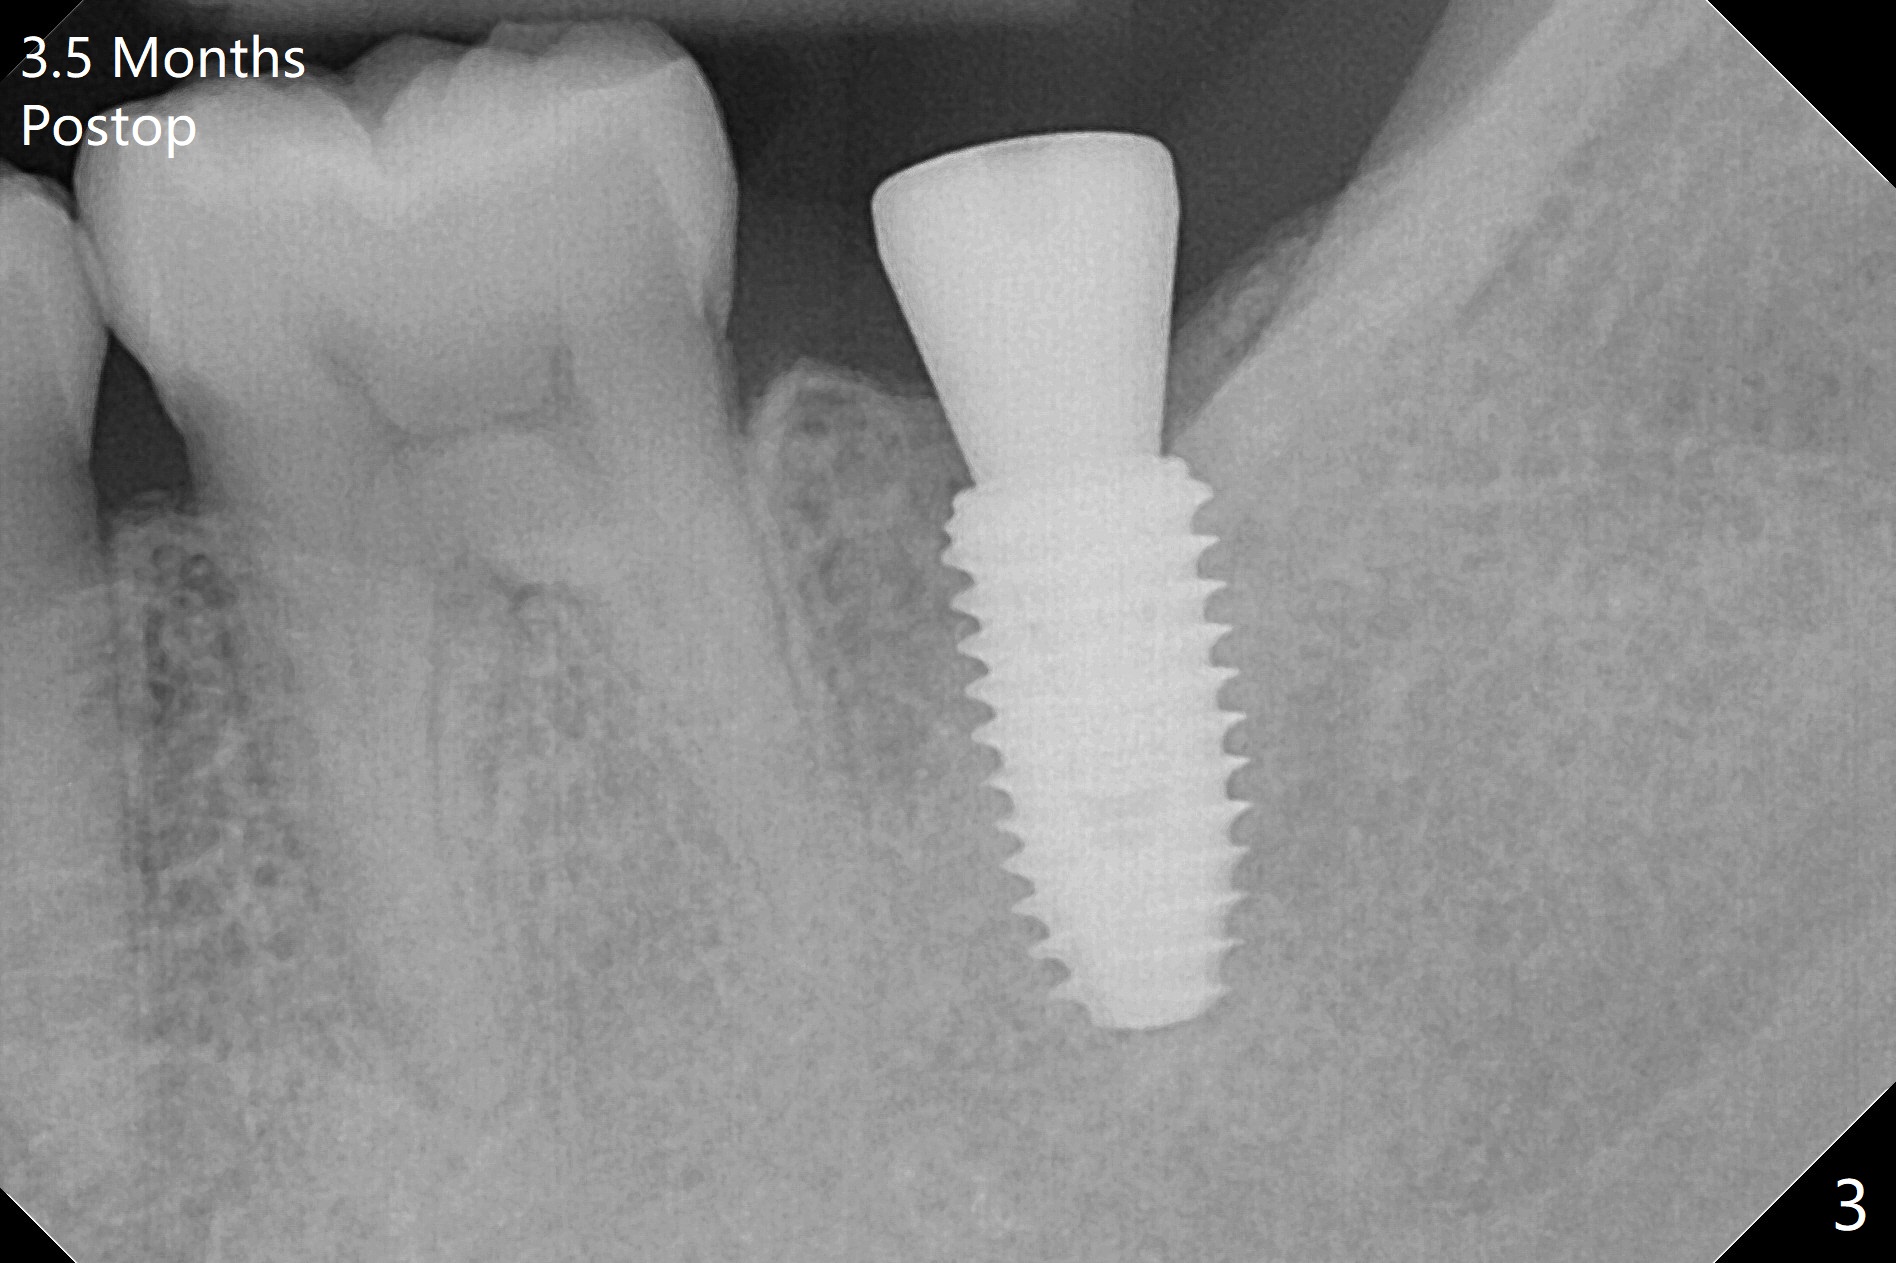

As usual, one ampule of 2% Xylocaine with 1:100,000 Epinephrine provides profound anesthesia and hemostasis at the site of #18. A 5x10 mm implant is placed with guided surgery in ~10 minutes. A shortage is low stability (10 Ncm), probably due to low bone density, which is not detected early (with increasing drill diameters). When a 5 mm tap is being used, there is basically no resistance. In fact the tap should be not used. When a 5.5x5 mm healing abutment is placed, hemostasis is achieved (Fig.1). There is sufficient clearance from the Inferior Alveolar Canal (red dashed line). More important is there is no risk of perforation of the lingual (L) plate as by design (Fig.2). There is no reported postop pain. There is no bone loss around the implant 3.5 months postop, which suggests that it is an atraumatic procedure (Fig.3). The all-purpose guide also allows neutral placement of the implant buccolingually (Fig.4), as compared to the partial one.